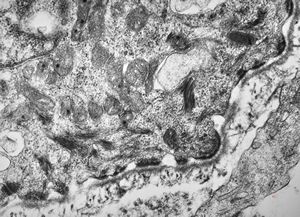

rat | skeletal muscle 6h. post ex. … changes of mitochondrial cristae